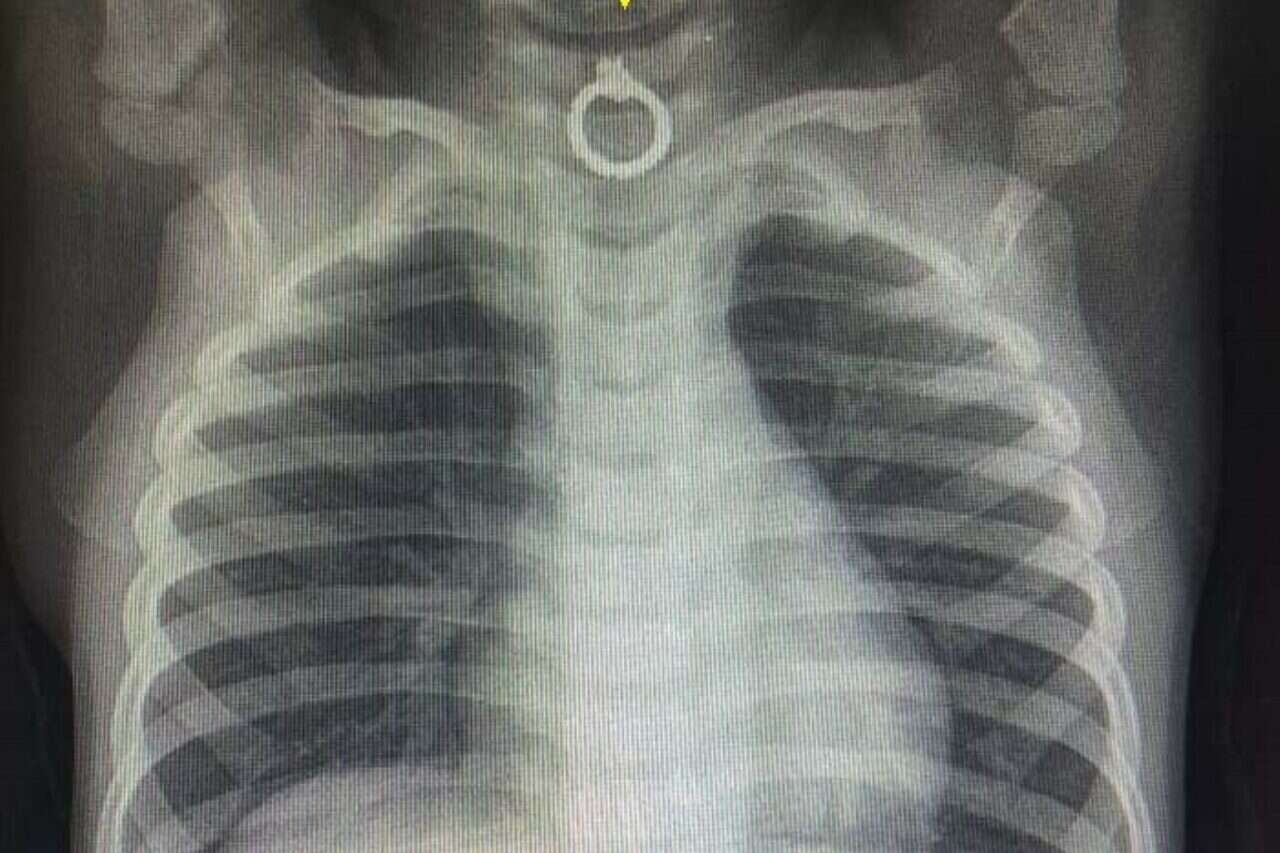

צילום: המרכז הרפואי זיו בצפת // צילום רנגטן של העגיל, בסמוך לקנה הנשימה

הצוות הרפואי ביצע בדחיפות צילום רנטגן וגילה כי הפעוט בלע עגיל טבעת מוזהב דק, שהתמקם באזור המסוכן בכניסה לוושט, בסמוך לקנה הנשימה.